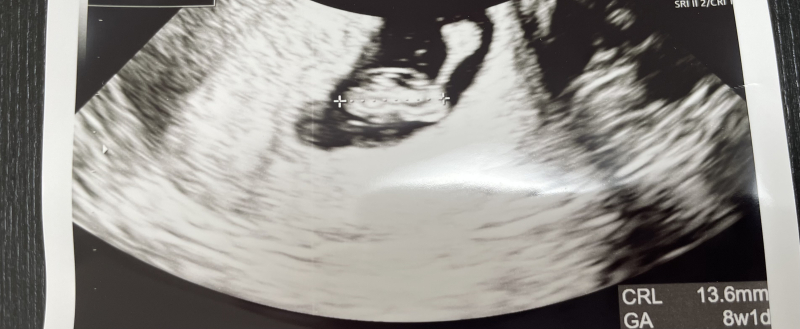

妊娠8週目くらいです。 エコー写真の中で 右上の丸から棒のように繋がっていますがこれは何でしょうか。 卵黄嚢だとしたらリング状なのかと思っていました。 何か心配になるようなことがあるのでしょうか。

エコーで気になる形のものが写っていたのですね。実際にエコーを拝見していませんし、私もあまり今まで見たことのない形ですので、何かということはなかなかはっきりとは分かりません。お役に立てず申し訳ありません。

確かに、卵黄嚢とは少し形が異なると思いますし、胎芽とも違うように思います。はっきりとしたことはわかりませんが、健診時に特に異常の指摘がないのでしたら、特にご心配な所見はないと思っていただいていいと思いますよ。